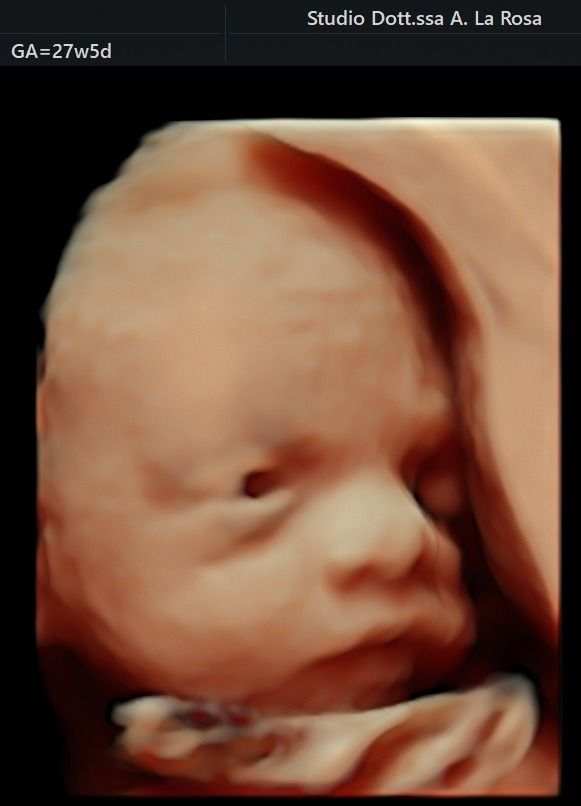

Nel corso della mia lunga esperienza lavorativa in ospedale,  ho maturato una particolare competenza nella gestione delle gravidanze a rischio sia per problematiche materne che fetali, nella diagnostica prenatale sia invasiva ( amniocentesi, villocentesi) con all'attivo migliaia di procedure effettuate, che nella diagnostica strumentale ecografica ( ecografie ostetriche di I e II livello, test combinato, studio della Translucenza nucale, DNA fetale, studio doppler flussimetrico dei distretti materni e fetali ).

Foto e video